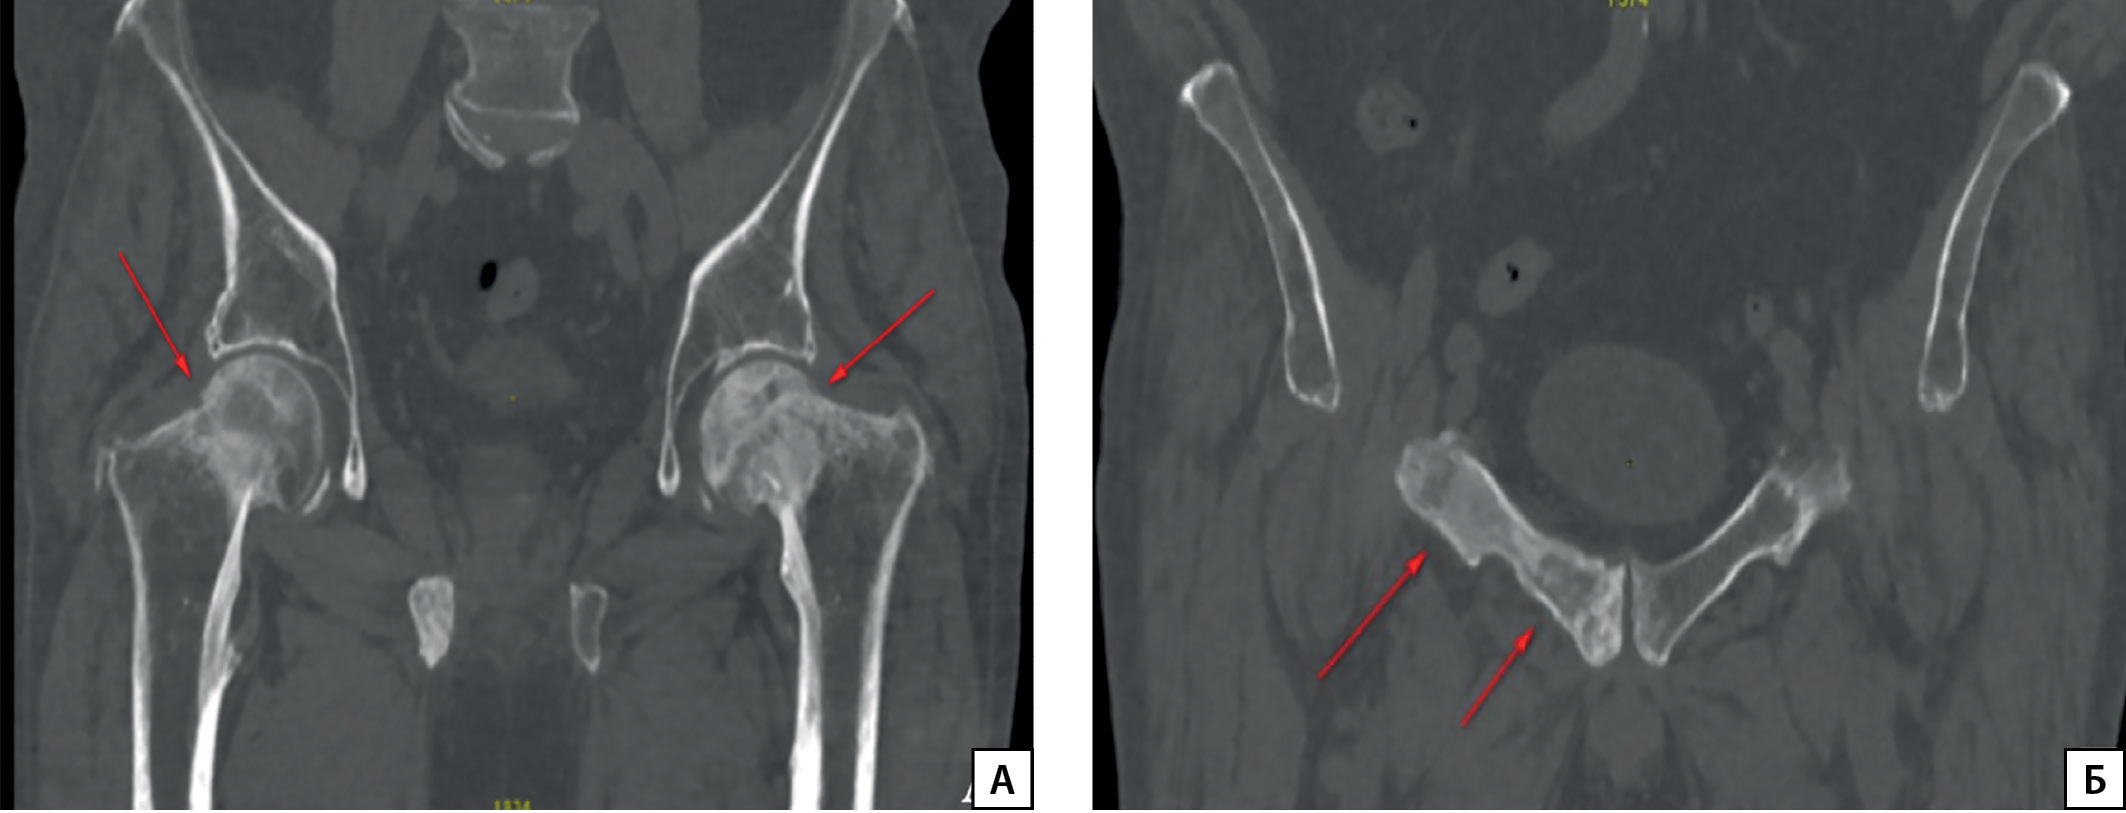

Рисунок 3.2. ОФЭКТ/КТ пациента П.

Описание: вздутие и неоднородность костной структуры переднего отрезка 3-го ребра справа (А) и заднего отрезка 6-го ребра справа (Б), кортикальный слой с неровными контурами с накоплением радиофармацевтического препарата (В, стрелки), плотность костной ткани повышена на всем протяжении (Г).

Для топической диагностики проведена соматостатин-рецепторная сцинтиграфия в режиме «все тело» с 99mTc-тектротидом. Отмечается гиперфиксация радиофармацевтического препарата в очагах пораженных костей (рис. 3.1, 3.2), что свидетельствует о наличии соматостатиновых рецепторов в этих участках, и, наиболее вероятно, метастатическое поражение является источником продукции ФРФ23.

Поиск ФРФ23-образований выполняют поэтапно. Вначале проводят «функциональную визуализацию», т.е. используют специфические радиофармпрепараты (РФП), которые накапливаются в ткани опухоли за счет наличия в ней соматостатиновых рецепторов 2А подтипа [27]. Применяется сцинтиграфия с РФП (99mTc-тектротид, 111In-октреотид) либо позитронно-эмиссионная томография с РФП (соли галлия: 68Ga DOTA-TATE/NOC). Затем осуществляют топический поиск опухоли: КТ, МРТ, УЗИ. При таком подходе удается верифицировать до 70% образований [28]. У пациента П. были обнаружены множественные очаги с гиперфиксацией РФП в очагах пораженных костей, что свидетельствует о наличии в метастазах соматостатиновых рецепторов,а значит, косвенно подтверждает секрецию ФРФ23.